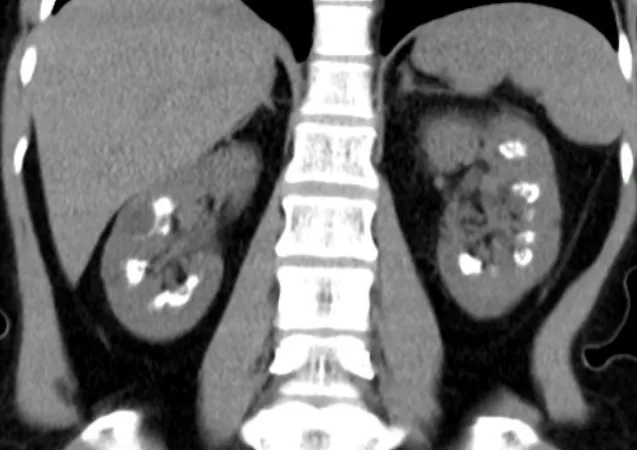

Uso do Tolvaptan na DRPAD: O Que falam nas Novas Diretrizes KDIGO 2025?

As novas diretrizes KDIGO para a Doença Renal Policística Autossômica Dominante (DRPAD) atualizam os critérios de elegibilidade para o uso de tolvaptana, com ênfase na estratificação do risco de progressão rápida. O documento reforça a individualização da terapia com base em subclassificação por imagem (Mayo Clinic) e função renal. A incorporação prática dessas recomendações pode otimizar o manejo e retardar a progressão da DRC nesses pacientes.